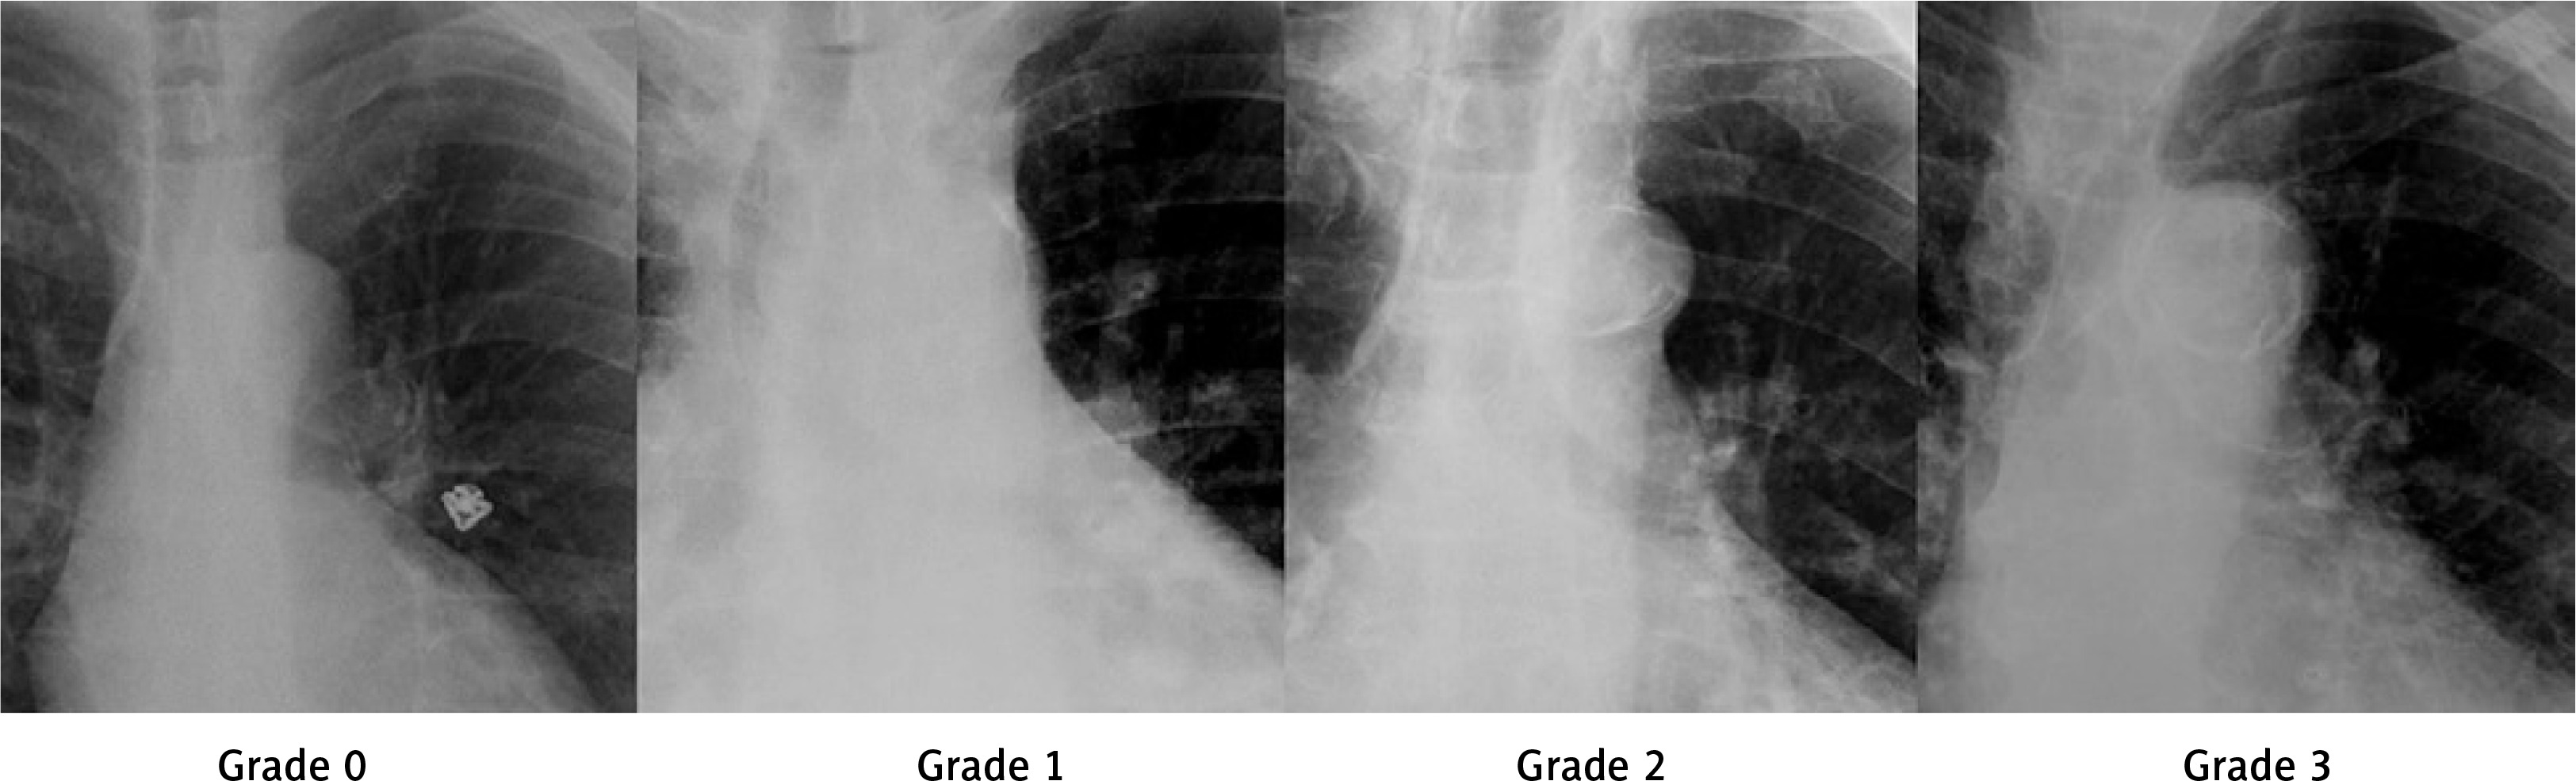

The chest radiographs of the patients were examined and graded for AKC, as described in recent studies [20]. The examination was performed using the following grading system: Grade 0, no calcification; Grade 1, point calcifications or small fine lines of calcification; Grade 2, thickened calcification in one or more areas; and Grade 3, circular thickened calcification (Figure 1).